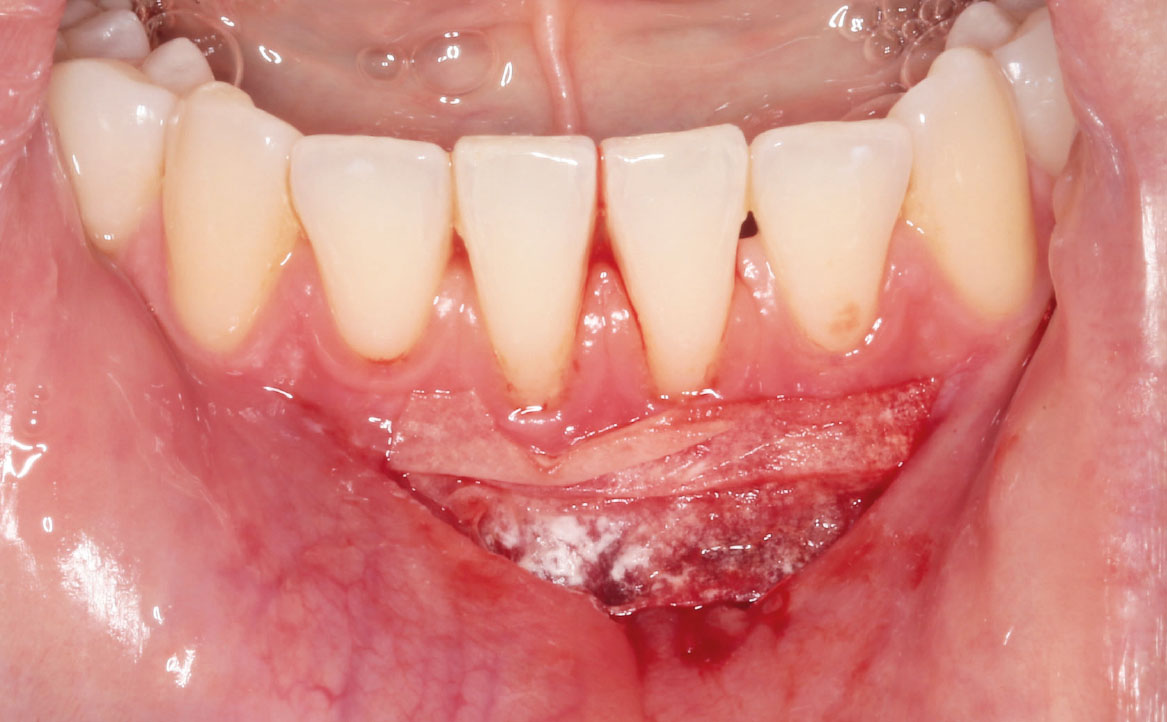

Infine, una membrana riassorbibile in pericardio suino è stata modellata secondo la forma della ferita (fig. 8) e, dopo averla idratata in soluzione fisiologica, è stata posizionata sul sito chirurgico (fig. 9) fissata con punti di sutura riassorbibili (fig. 10). La membrana riassorbibile in pericardio suino è un materiale reso altamente biocompatibile grazie ai processi di rimozione di cellule e lipidi eseguiti con anidride carbonica supercritica (14). La membrana svolge un’azione barriera separando la ferita chirurgica dall’ambiente del cavo orale. Inoltre, favorisce l’adesione cellulare e ricopre un importante ruolo nella promozione della formazione e della stabilizzazione del coagulo (15,16). Studi condotti sull’effetto combinato dell’acido ialuronico reticolato e della membrana riassorbibile in pericardio suino dimostrano un rallentamento della degradazione della membrana e un potenziamento degli effetti del glicosamminoglicano (17).